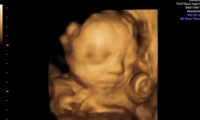

Sondenreparatur bei Schäden an 3D/4D Sonden

Defekte an Kabeln oder am Knickschutz sind gängige Schäden und ein Fall für eine Sondenreparatur Bei defekten Kabeln ist eine…